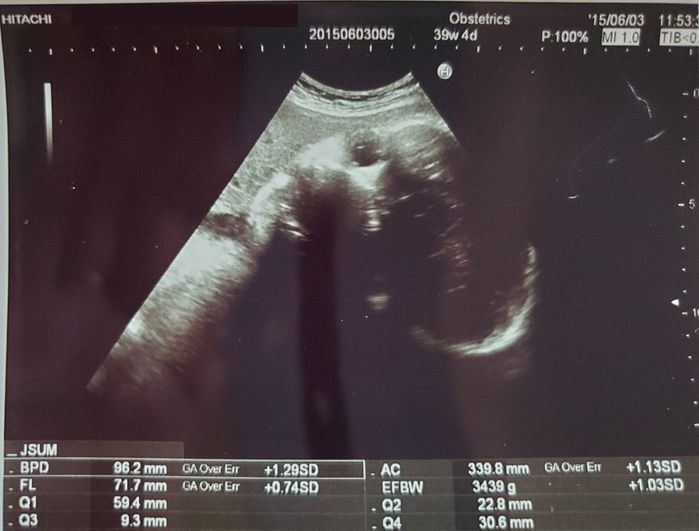

妊娠39週目のエコー写真 - いよいよ出産間近!? ドキドキの毎日

順調に大きくなる赤ちゃん。EFBW(胎児推定体重)も3400gを超えてグングン増え、先生に「大きいね」と言われていました。やはり今回のエコーもこちらを向いていて、じっと見つめられている気分です。このころ、おなかはパンパン。何をするにもおなかが重く、腹帯の上にさらしをグルグルに巻いておなかを支えていました。腹囲は97cmありました。